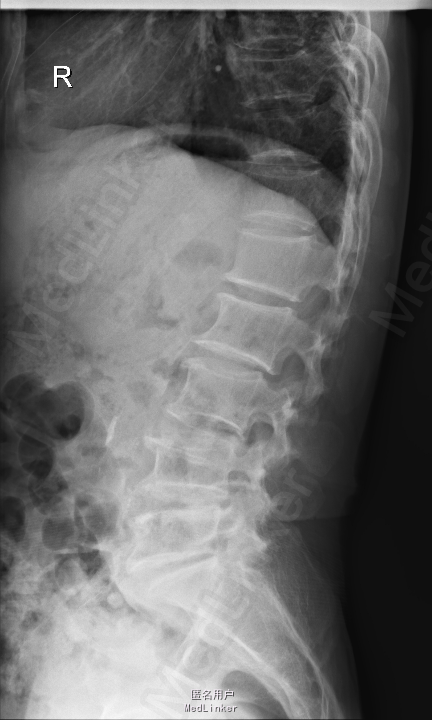

腰痛5年,加重伴左下肢放射性疼痛半个月 患者5年前无明显诱因出现腰痛,不伴下肢放射性疼痛、麻木、无力,腰部活动受限,劳累后加重,平卧休息可缓解。半个月前无明显诱因出现腰痛加重,伴左下肢放射性疼痛、麻木,腰腿活动受限,无低热、盗汗,无纳差、消瘦。

查体:左侧小腿外侧、足背感觉减退,右侧正常,双侧屈髋、伸膝、踝背伸肌肌力5级,左侧踇背伸、跖屈肌肌力4级,右侧踇背伸、跖屈肌肌力4-5级,双侧巴氏征阴性,直腿抬高试验左侧30°阳性,右侧阴性。 辅助检查: X-ray:腰椎退行性变,腰椎节段性性不稳 MR:腰椎间盘突出,腰3/4,4/5,腰4/5节段明显

诊断:腰椎椎管狭窄 处理: 1、完善相关辅助检查,明确诊断,有无手术指证; 2、完善手术评估,有无手术禁忌,手术风险及并发症; 3、在全麻下行腰椎后路减压,腰3/4左侧椎板减压,腰4/5椎间Cage植骨融合内固定术